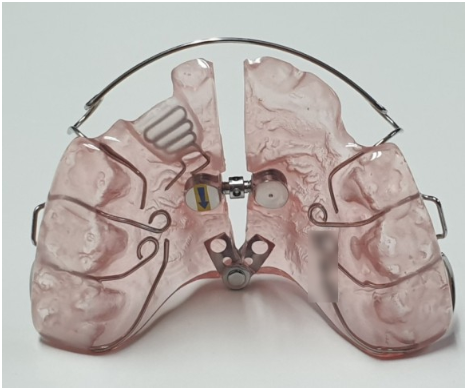

따라서 망우동 교정치과 에서는

‘Fan type expander(전치 확장장치)’를 사용하여

배열할 공간을 확보하기로 했습니다.

이는 가철성 장치로

구치부 이동이 거의 없는데요.

위 사진과 같이 부채꼴처럼 벌어지면서

전치 배열 공간을 확보할 수 있습니다.